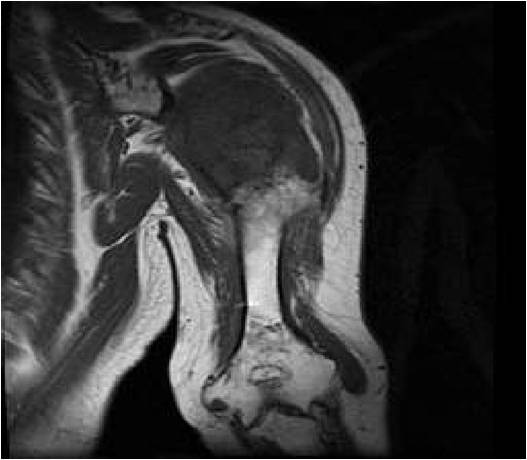

MRI:

- Lobulated margin (Lobular Growth Pattern)

- T1 Weighted Images: Intermediate Signal Intensity

- Calcifications will be low signal

- T2 Weighted Images: High Signal Intensity

- High water content shows as high signal on T2 weighted images

- Marked increased intensity long TR images

- Calcified chondroid – low intensity all sequences

- There should never be any cortical destruction nor a soft tissue component. If this exists then the tumor must be a chondrosarcoma.

- Endosteal scalloping and cortical expansion is acceptable for phalangeal tumors. In most benign long bone cartilage tumors there is minimal endosteal scalloping but there should be no cortical expansion nor thickening. There should be no cortical destruction and no soft tissue component associated with an enchondroma. Cortical destruction, periosteal thickening, cortical expansion and a soft tissue component indicates a chondrosarcoma of the long bone.

T1: Intermediate Signal Lobular Growth